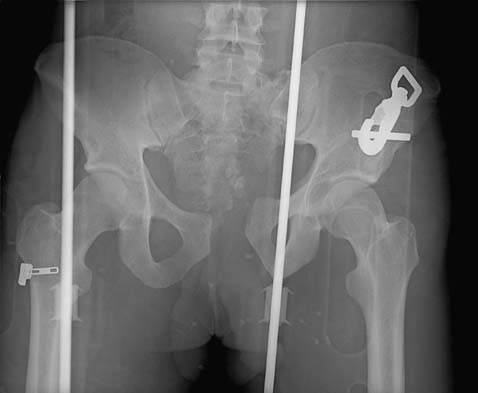

- Radiographs

- recommended views

- AP

- part of initial ATLS evaluation

- look for asymmetry, rotation or displacement of each hemipelvis

- evidence of anterior ring injury needs further imaging

- CT

- routine part of pelvic ring injury evaluation

- better characterization of posterior ring injuries

- helps define comminution and fragment rotation

- visualize position of fracture lines relative to sacral foramina